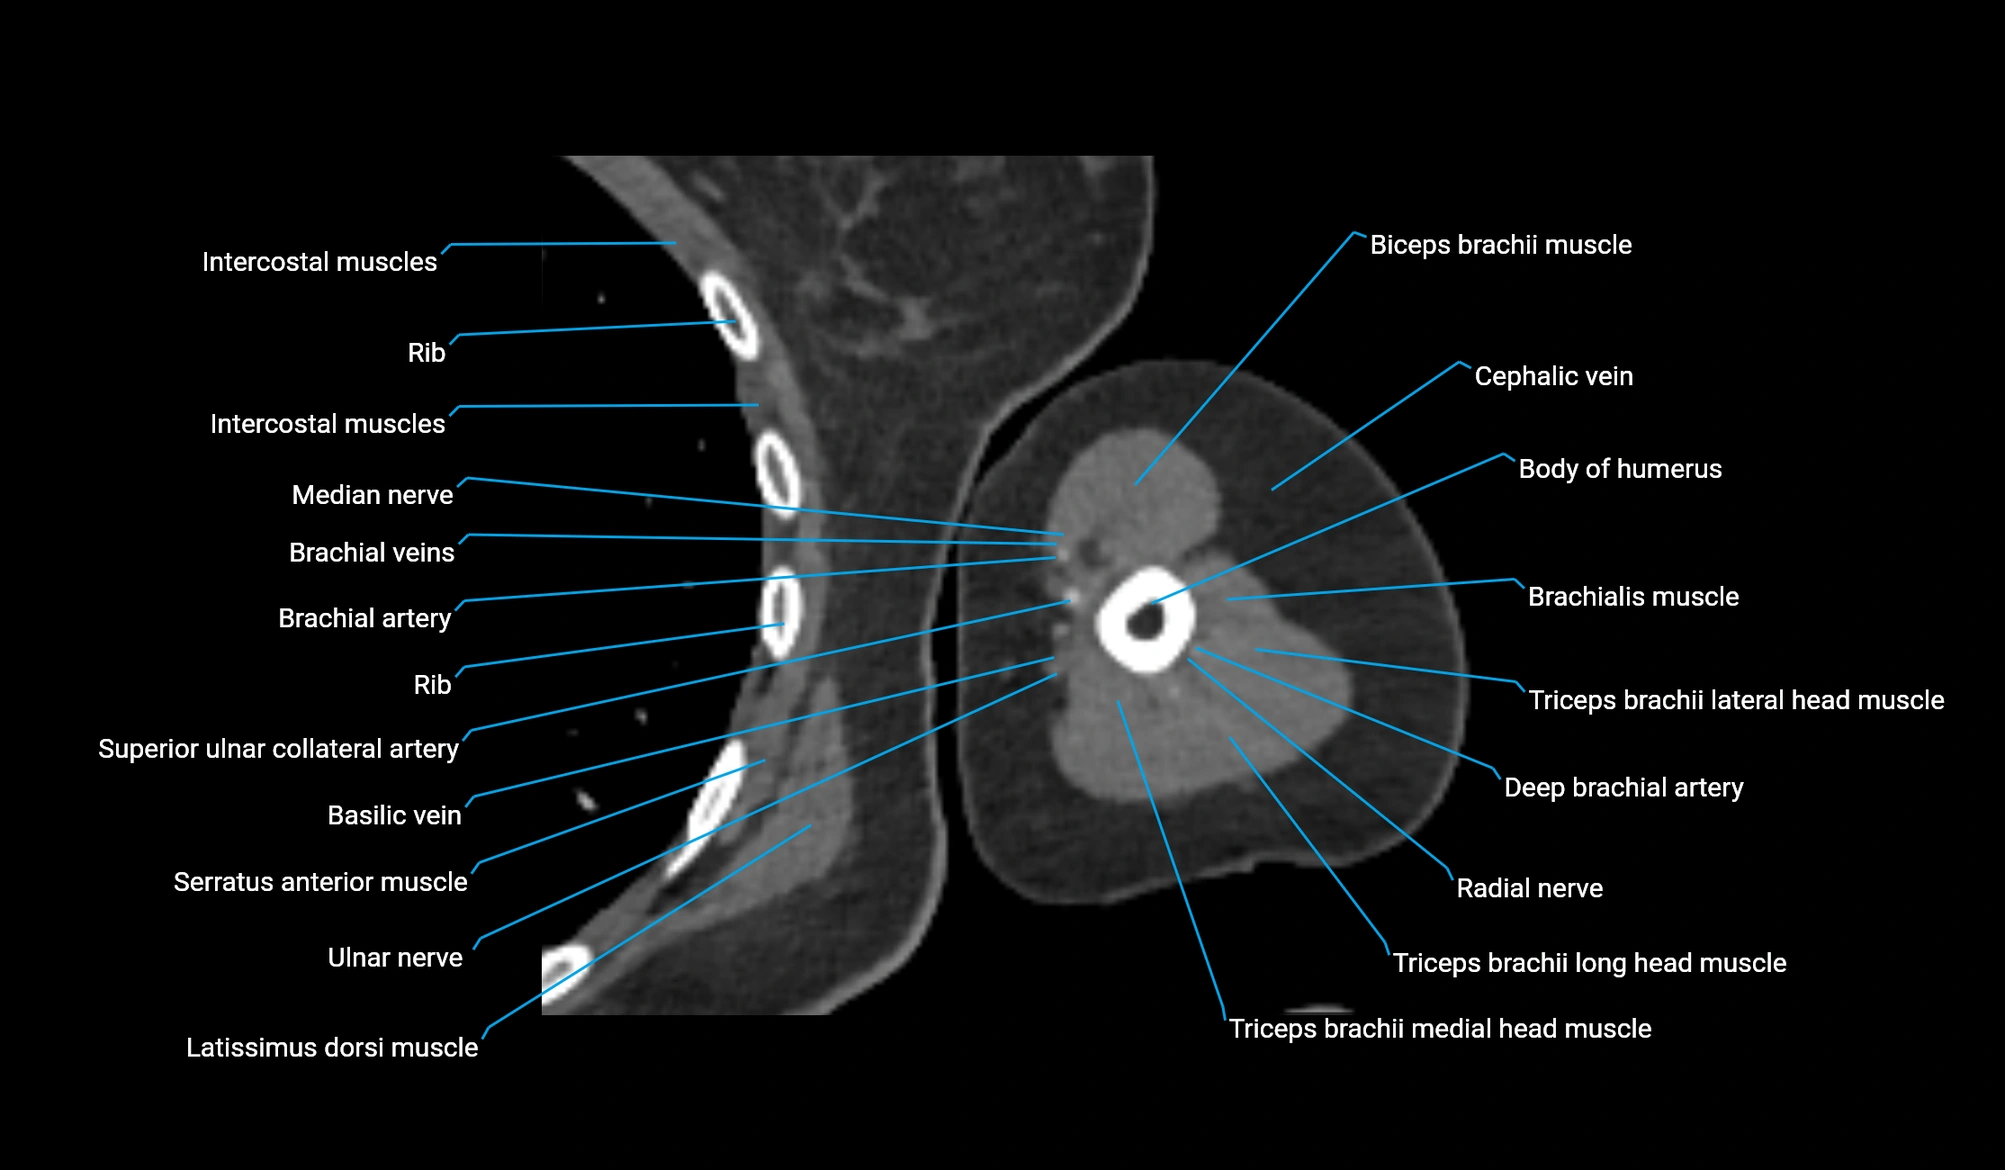

- Body of humerus

- Biceps brachii muscle

- Cephalic vein

- Brachialis muscle

- Deep brachial artery

- Brachial artery

- Superior ulnar collateral artery

- Basilic vein

- Ulnar nerve

- Median nerve

- Long head of triceps brachii muscle

- Lateral head of triceps brachii muscle

- Medial head of triceps brachii muscle